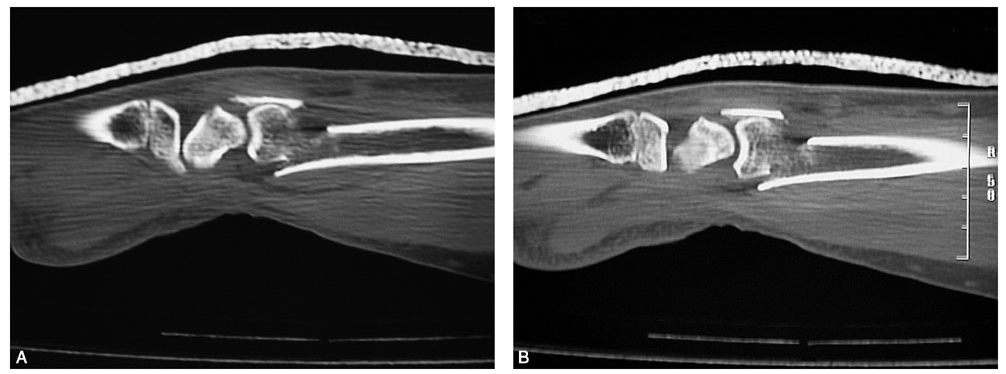

患者,女,51岁。因右腕摔伤后肿痛、畸形、活动受限,急诊就诊诊断为右桡骨远端骨折。行闭合牵引复位,石膏托外固定。拍片复查,桡骨远端背侧因骨折的粉碎性质而缺损巨大,背侧的皮质骨碎片向远端移位至桡腕关节间隙水平并嵌于腕背软组织中无法闭合复位(图2-1)。桡骨远端背侧因缺乏可靠的皮质骨支撑而存在骨折继发移位、掌倾角向背侧倾斜且移位的皮质骨碎片潜在刺激背侧软组织、磨损伸肌腱的风险,增加发生关节疼痛和功能障碍的可能性,于是行桡骨远端骨折切开复位,人工骨植入,超关节外固定架固定术。

图2-1 桡骨远端背侧因骨折的粉碎性质而缺损巨大,背侧的皮质骨碎片向远端移位至桡腕关节间隙水平并嵌于腕背软组织中无法闭合复位

术前拍腕关节正、侧位X线片,腕关节冠状位、矢状位和水平位CT(图2-2)。此患者骨缺损和无法闭合复位的骨片均在背侧,宜采用背侧入路,复位,植骨,固定。取患肢前臂远端桡背侧纵切口(图2-3),从伸拇长肌腱和桡侧伸腕长、短肌之间进入,注意保护血管神经和肌腱,显露清理折端骨缺损区域和背侧移位的骨片(图2-4),复位,植骨,外固定架超关节固定(图2-5、图2-6)。术中透视骨折复位固定满意(图2-7),术后拍X线片证实(图2-8)。此手术的优点在于避免了局部存在内固定物的刺激,避免二期切开取出固定物所致的再次损伤。

图2-2 骨缺损和无法闭合复位的骨片均在背侧